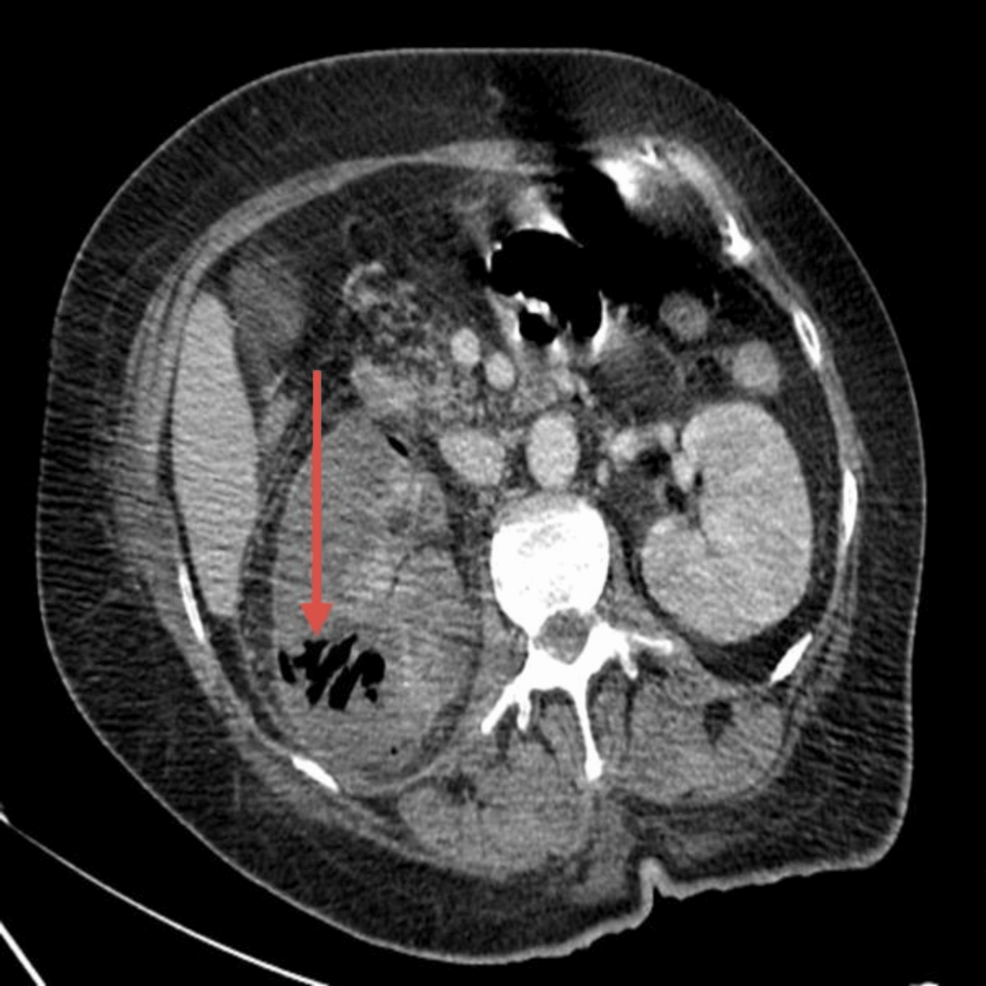

The answer to last week's #SARgettable Case of the Week, submitted by @kchang, is: Renal Tuberculosis (putty kidney) and Tubercular Spondylitis (Pott disease). Thanks for playing!